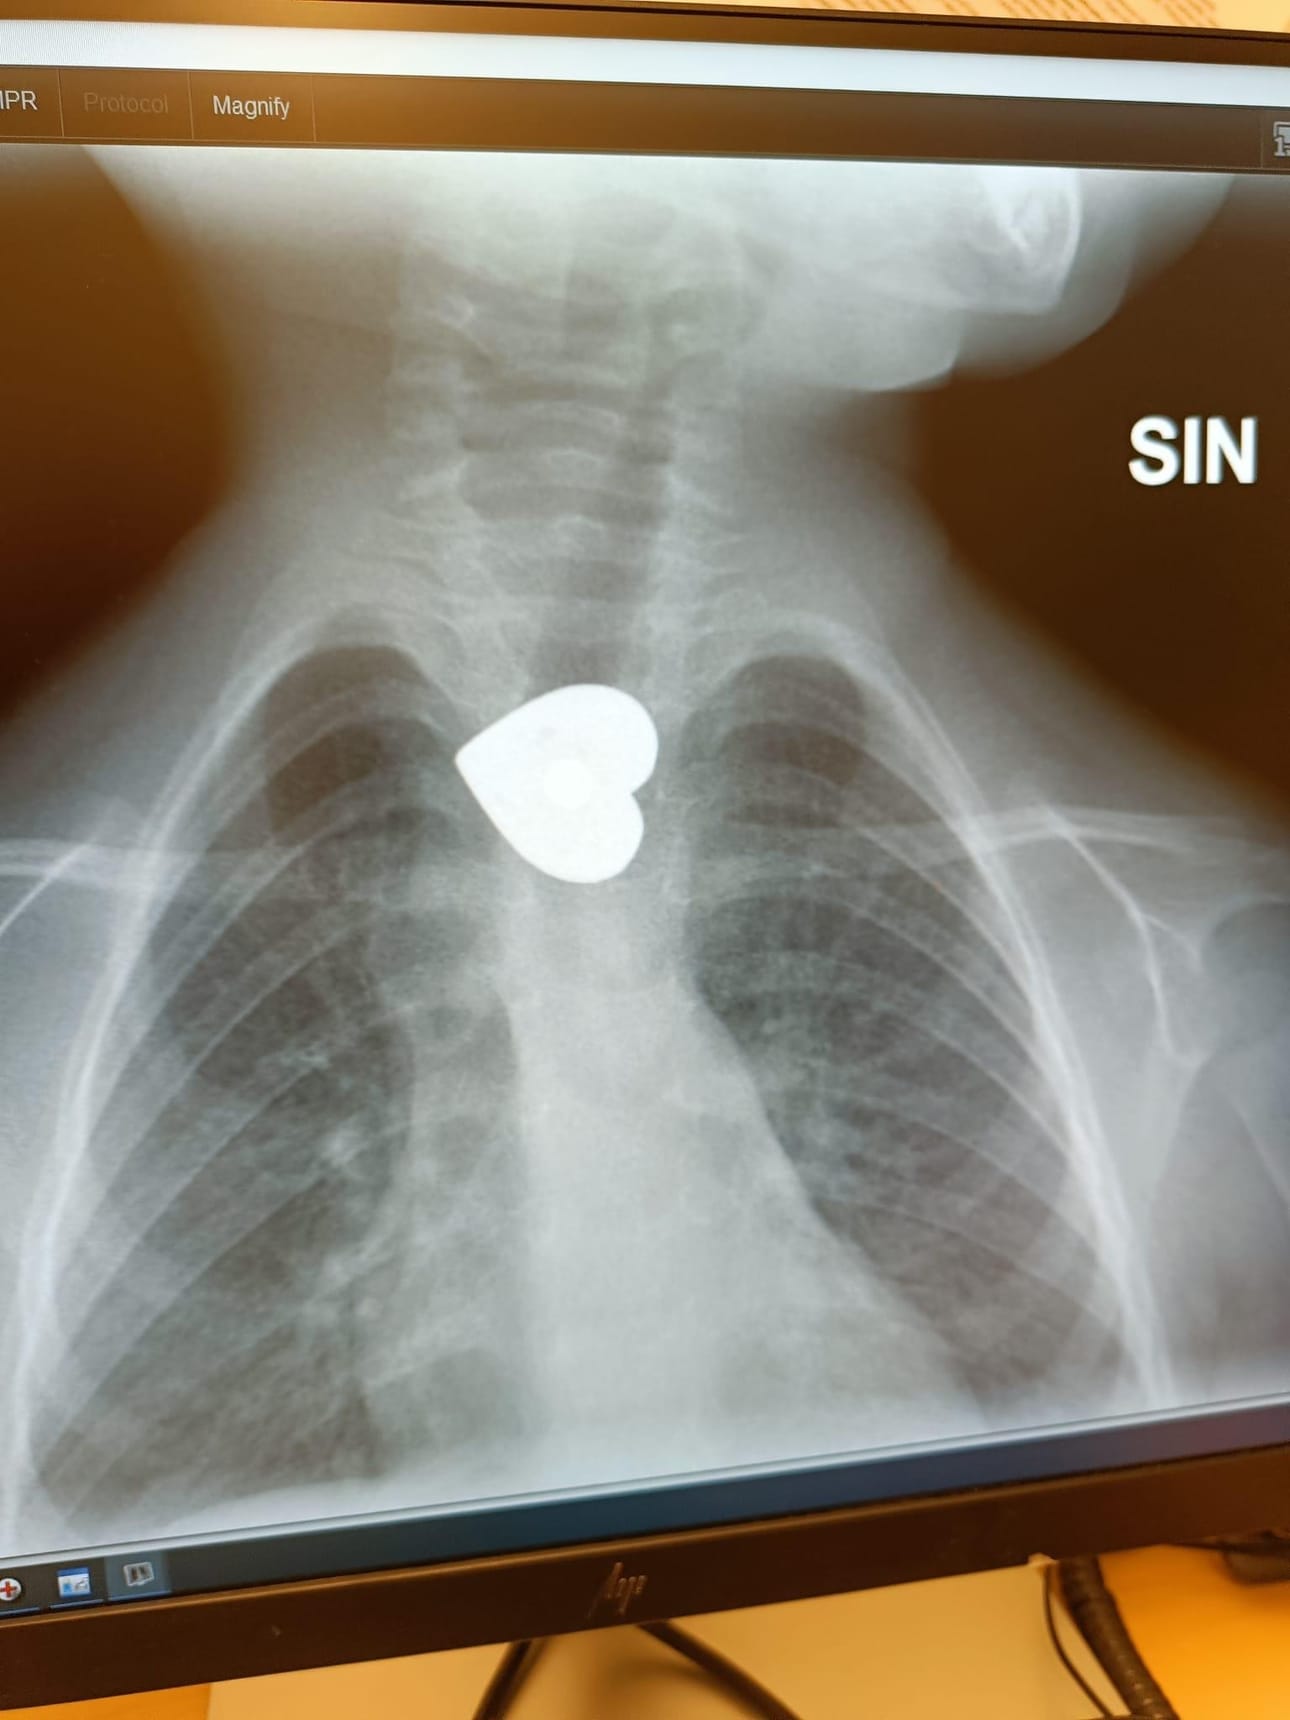

Alle 3-vuotias poika nielaisi magneetin, joka näkyi röntgenkuvassa erittäin selkeänä sydämenä. Esine poistettiin nukutuksessa OYSissa. Kuva on otettu tietokoneen näytöltä, jossa näkyy Länsi-Pohjan sairaalan ottama röntgenkuva.

Kuva: Martti Holappa

Kemiläisen perheen viikonloppu sai hätkähdyttävän käänteen, kun hieman alle kolmevuotias Roni-poika nielaisi sydämenmuotoisen magneetin.

– Poika tuli keittiöstä ja kertoi, että minä nielaisin magneetin, isä Martti Holappa kertoo.